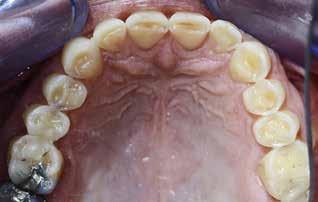

BAGGRUND – Denne kasuistik beskriver en patient, hvor der blev valgt protetisk behandling i ung alder.

PATIENTTILFÆLDE – En niårig pige havde stort behandlingsbehov og smerter fra tænderne på grund af tandudviklingsforstyrrelse. Der var flere gange forsøgt restaurering med komposit, som ikke fungerede. Laminater i feldspatkeram blev valgt for at fjerne mindst mulig tandsubstans, øge holdbarheden på restaureringerne og forbedre æstetikken. Patientens motivation, meninger og kooperationsevne var vigtige for behandlingsvalget, da behandlingen var tidkrævende og til tider udmattende for en ung patient.

KONKLUSION – Resultatet var vellykket og medførte forbedret livskvalitet. Protetisk behandling med adhæsiv teknik kan være et godt behandlingsalternativ for børn og unge på ret indikation.

EMNEORD Adhesives | amelogenesis imperfecta | ceramics | pediatric dentistry | quality of life

Protetisk behandling med adhæsiv teknik –et alternativ i ung alder?

Accepteret til publikation den 26. marts 2024 Tandlægebladet 2024;128:758-62

VED BEHOV FOR OMFATTENDE TANDRESTAURERING HOS BØRN OG UNGE kan flere behandlingsalternativer være aktuelle (1). Restaurering med fyldningsmaterialer er som regel førstevalg, men i nogle tilfælde fungerer dette ikke godt nok. Ved udarbejdelse af behandlingsplan må klinikerne kende til mulige behandlingsalternativer og vurdere disse på baggrund af kliniske fund, patientens symptomer og kooperationsevne samt patientens ønsker og planlægge behandling i et livsløbsperspektiv.

PATIENTTILFÆLDE

Beskrivelse af patienten Patienten blev henvist til specialistuddannelsen i pædodonti ved Universitetet i Oslo, da hun var syv år gammel, for diagnostik og behandling af tandudviklingsforstyrrelse i primære og permanente tandsæt. Pigen havde pollenallergi, var ellers sund og rask og havde intet medicinforbrug.

Klinisk undersøgelse viste emaljehypoplasier og hypomineralisering på 1+, +1, 2-, 1-, -1 og -2 (Fig.1). Hun havde Angle klasse II, pladsmangel i begge kæber og agenesi af -5. Der var isninger ved spisning og tandbørstning. Fundene var forenelige